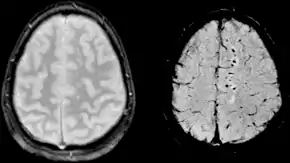

Two MRI images of a patient with diffuse axonal injury resulting from trauma, at 1.5 tesla field strength. Left: conventional gradient recalled echo (GRE). Right: Susceptibility weighted image (SWI).